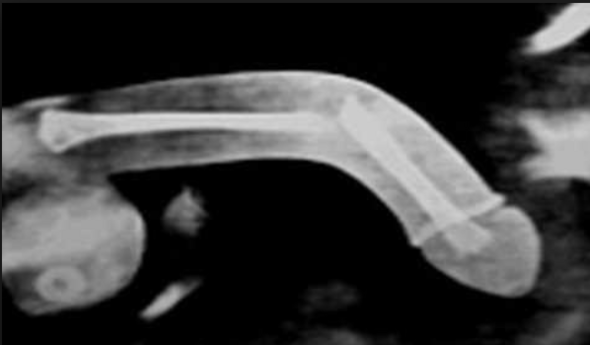

The foreskin, after being pulled back, becomes trapped behind the head of the penis;. Men who are serious about enlarging their penis should read the book, Iron Man Penis The Russian System The Third Edition has just been released with some fantastic and unique methods of Penis EnlargementSuch a book introduces men to Penis Exercising techniques that aren't just a regurgitation of the same information that's been recycled to death on the Internet. Dieses Bild schockt Ärzte Mann hat Knochen im Penis Verletzungen und Geschlechtskrankheiten wie Syphilis und Gonorrhö können ebenfalls dazu führen, dass sich Kalzium im Penis ablagert.

Ein 63jähriger Mann aus New York ging nach einem Sturz mit Schmerzen im Knie ins Krankenhaus Befund Mann hat einen Knochen im Penis!. This is a medical emergency because it can cause permanent damage to the penis You should see your doctor immediately. The ridged band is the interface (join) between the outer and inner foreskin layers.

Darum haben Männer keinen Knochen im Penis Viele Säugetiere besitzen einen Penisknochen, Menschen nicht Sie müssen sich beim Sex allein auf Schwellkörper verlassen. Knochen im Penis Mit diesem Zufallsfund hatte niemand gerechnet PenisVerletzungen und Geschlechtskrankheiten wie Syphilis und Gonorrhö können dazu führen, dass sich Kalzium im Penis ablagert. Knochen, der sich im Penis der meisten Säugetiere befindet, jedoch nicht beim Menschen Übersetzungen Penisknochen Hinzufügen báculo noun de Knochen es hueso peneano 1 Definitionen @omegawiki Algorithmisch generierte Übersetzungen anzeigen Bildwörterbuch báculo Beispiele Hinzufügen.

Rontgenbild Enthullt Arzte Schockiert Patienten Penis Wird Zu Knochen News De